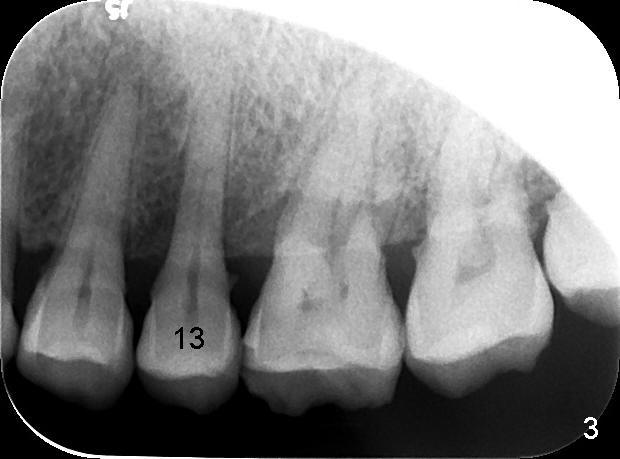

A 57-year-old man has history of chronic periodontitis (Fig.1,2, taken 9 and 7 years ago, respectively). Last April the tooth #13 had crown fracture (Fig.3). He returned to clinic for scaling & root planing last week (Fig.4). Fig.3,4 show long root and bone. Arrowheads in Fig.4 indicate the sinus floor.